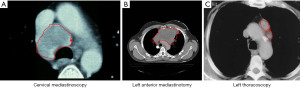

In case more adequate tissue is desired for histology, immunohistochemistry, and molecular testing to fully characterize the tumor, a surgical biopsy either minimally-invasive or occasionally via open way may be needed to obtain more tissue for histopathology and immunological staining. Depending on the exact location of the mass in any mediastinal compartment (Figure 2), different surgical approaches can be chosen varying between median or lateral cervical incision for highly located prevascular tumors, anterior mediastinotomy for parasternal lesions in the prevascular mediastinum; video-assisted mediastinoscopy as an alternative to EBUS or EUS for a mass in the visceral mediastinum; or video-assisted (VATS) or robot-assisted (RATS) thoracoscopy to biopsy a lesion in the prevascular or paravertebral mediastinum. Minimally invasive procedures such as VATS and RATS offer the possibility to also sample hilar or pleural abnormalities concomitantly identified. Occasionally a partial sternotomy or limited thoracotomy may be needed to reach the tumor for adequate tissue biopsy. In one study in patients with a suspicion of a lymphoproliferative disease extending in the prevascular and visceral compartment, the authors reported that diagnostic accuracy was lower for cervical mediastinoscopy (80.4%) compared to anterior mediastinotomy (95.9%) (30).